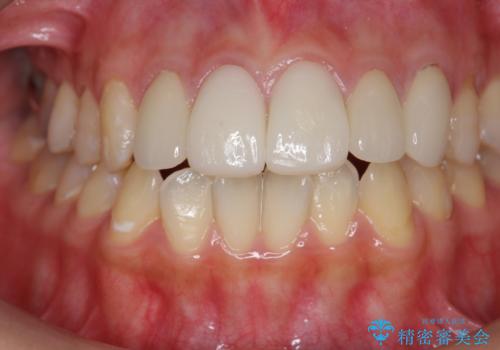

不適合なクラウンのやりかえ

- 数ヶ月前に他院で装着したセラミッククラウンから、歯ブラシのたびに出血することの改善を求めて来院されました。

X線写真よりクラウンの際があっていない状態であることがわかり、再度精度の良いセラミッククラウンを製作していくこととなりました。

- 22万円(仮歯・ジルコニアクラウン×2)費用は治療当時の料金となります

残存している歯と、クラウンの合いが悪い(不適合クラウン)歯汚れは溜まりやすく歯ぐきが腫れ虫歯・歯周病の再発リスクを高めます.